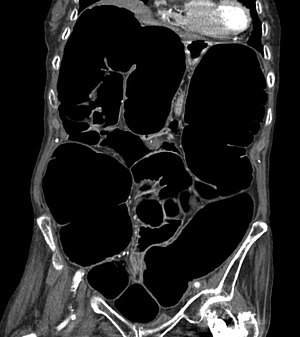

| CT scan of the abdomen of an elderly woman with Ogilvie syndrome | |

It generally occurs in those with significant health problems or following surgery.[2][1] While the underlying mechanism is unclear, it is believed to involve poor contraction of the colon.[3][1] Generally the cecum has a diameter of more than 10 cm and right colon is also dilated.[4] A CT scan or water-soluble enema is done to rule out a obstruction.[1]